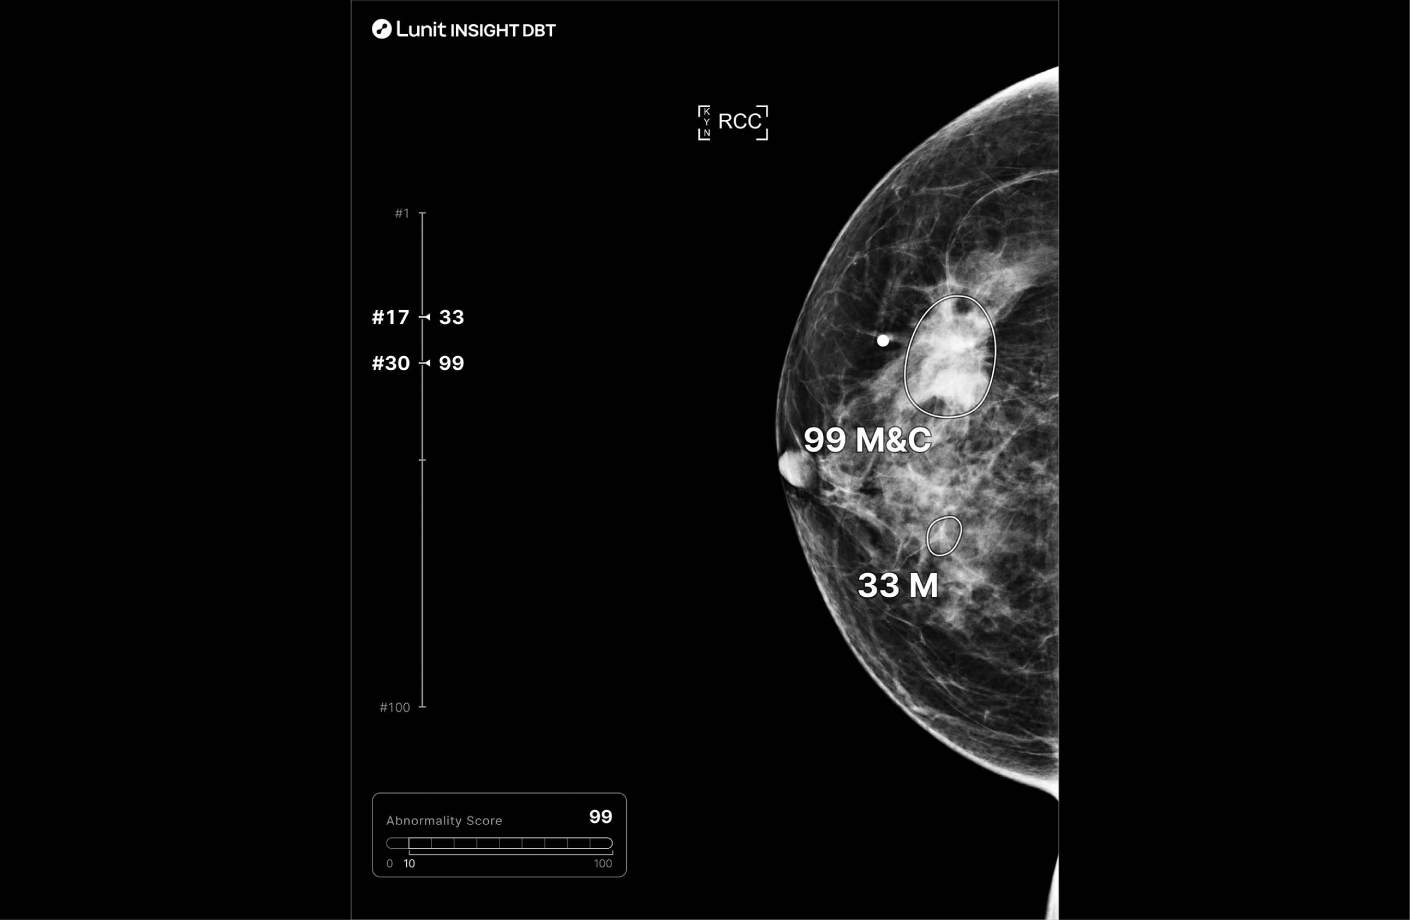

루닛 인사이트 DBT는 유방단층 촬영 영상을 분석해 유방암 의심부위의 위치와 유방 내 병변이 존재할 가능성을 0~100 범위의 점수로 표시합니다.

또한 병변 유형을 세 가지로 표시합니다.

분석결과는 별도 생성되는 영상 혹은 원본 영상 위에서 확인할 수 있습니다.